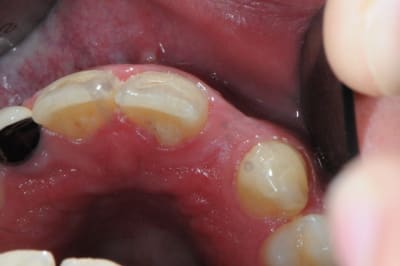

dentiste57

agénésie de 12,

extraction de 52 depuis 2 ans et remplacement par un mainteneur d'espace, vient consulter pour un implant...

j'adore ce genre de cas, c'est un vrai défi esthétique où on a pas le droit à l'erreur.

je pense qu'une greffe osseuse serait peut être nécessaire pour la concavité. Toutefois, je devrais pouvoir m'en sortir en dilatant la crête osseuse vestibulaire pendant la pose de l'implant.